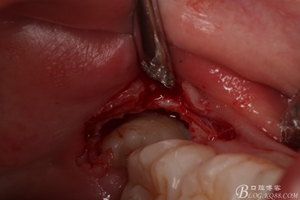

圖6.麻醉效果確定后,在37的近中做垂直松弛切口+遠中水平切口

圖7. 遠中的水平切口

圖8. 翻瓣:建議翻小瓣

圖9.翻開瓣,可見38部分牙冠暴露